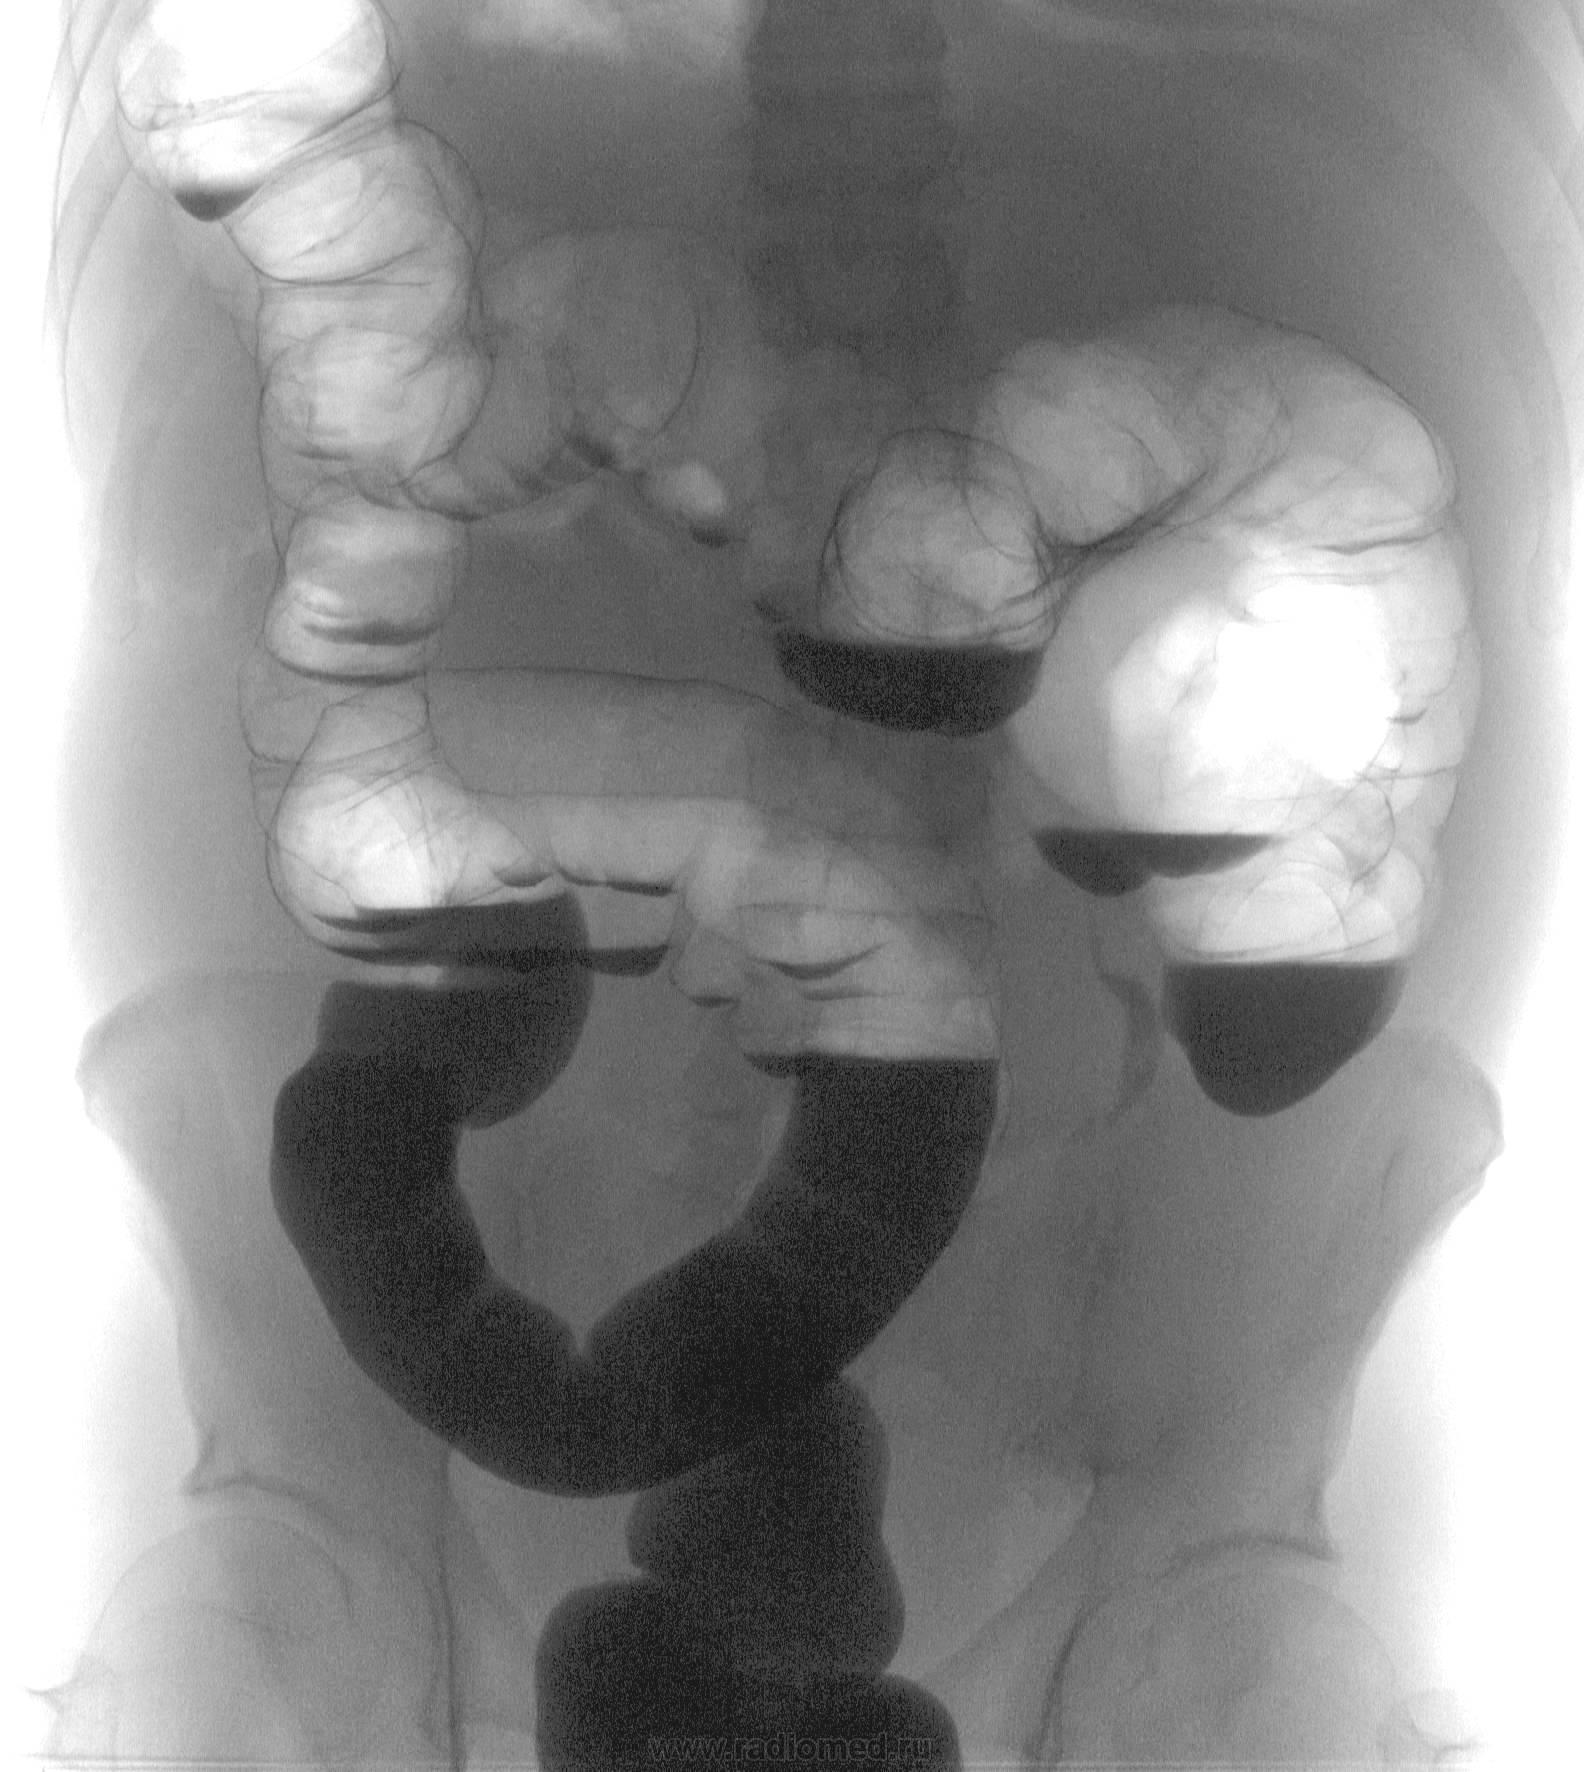

Пациент стоит лицом к трубке...потому тут все "наоборот" как бы...в действительности с топографией все обычно...вот разве что сигма "удлинилась"))), да слепая "загуляла"))))

Насколько я в курсе, современной методикой ирригоскопии признано первичное двойное контрастирование, подразумевающее "обмазывание" барием основной поверхности стенок кишки. Естественно, если сделать снимок в положении стоя, неизбежные "излишки" тяжелого бария стекут в отлогие места, оставив остальную кишку раздутой воздухом. Что и имеем в данном случае.

НИКОГДА не делал т.н. "трехэтапную" ирригоскопию (тугое-опорожнение-раздувание)...долго, громоздко, неудобно, и не всегда, мягко говоря, информативно...только одномоментное первичное двойное контрастирование, а оно предусматривает исследование (в т.ч.) как в вертикальном положение так и в положениях латероскопии (на левом и правом боках) горизонтальным лучом ...цель одна - получить в двойном контрастировании изображение ВСЕХ отделов толстой кишки.

Какая непроходимость? Это же ОБЫЧНАЯ картина ирригоскопии в ВЕРТИКАЛЬНОМ положении ....